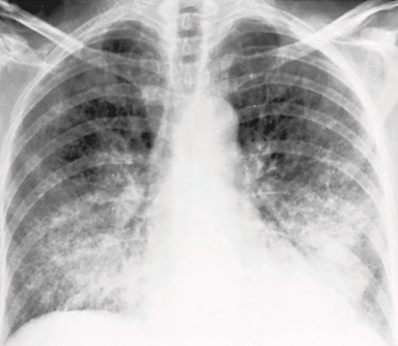

Describe the RA for alveolar pneumonia (this pic and pic in description)

homogenous consolidation in segments or the entire lung — air bronchograms are present (when an entire lobe fills with fluid but has not collapsed)

PT is 43 yr old male presenting with productive cough and fever/chills

What pathology is present?

pneumonia — alveolar/pneumococcal pattern